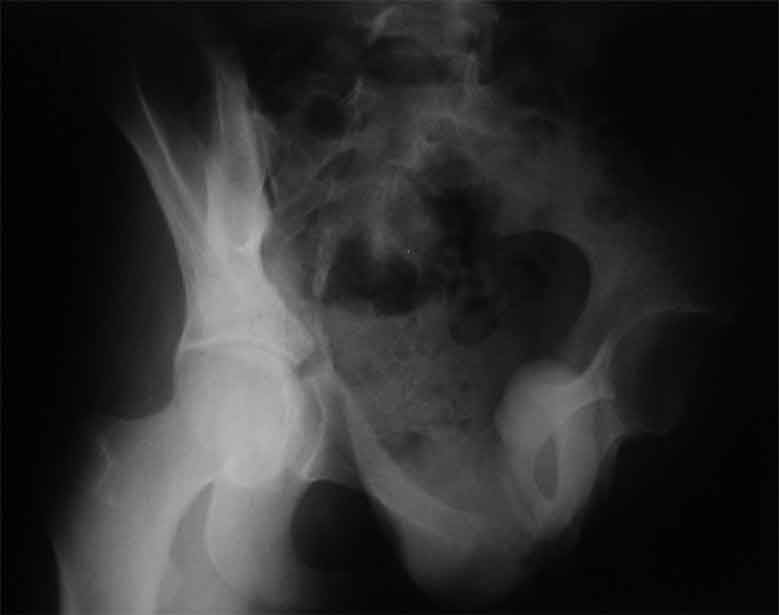

Уважаемые коллеги, сложный случай, интересует ваше мнение. Травма 2 месяца назад, в результате ДТП. При поступлении в лечебное учреждение по м/ж выполнено формирование культи на уровне в/3 левого бедра по (травматический дефект левой н/конечности), в послеоперационном периоде раневая инфекция, остеомиелит - экзартикуляция.

Повреждение таза лечилось консервативно. Интересует ваше мнение по поводу тактики лечения, попытаться свести аппаратом, а потом открытый этап (каким доступом/доступами)? другие варианты? С уважением Максим Агалаков